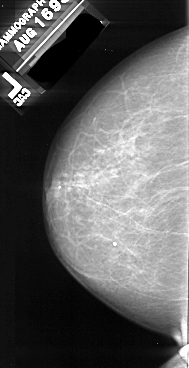

A_1085_1.LEFT_MLO

A_1085_1.LEFT_CC

LEFT_CC LINES 5881 PIXELS_PER_LINE 3016 BITS_PER_PIXEL 16 RESOLUTION 42 NON_OVERLAY

LEFT_MLO LINES 5986 PIXELS_PER_LINE 3151 BITS_PER_PIXEL 16 RESOLUTION 42 NON_OVERLAY